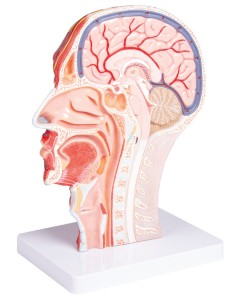

Dal cranio in 22 parti con incastri magnetici ai modelli di colonna vertebrale, da quelli di articolazioni a quelli di cuore, ogni pezzo della nostra collezione è progettato per un’immersione totale nello studio dell’anatomia umana. I nostri modelli, realizzati tramite scansioni di ossa vere, garantiscono un’esperienza tattile autentica e una fedeltà di peso quasi identica agli originali.

Essenziali per studenti e professionisti, i nostri modelli anatomici sono strumenti didattici che permettono di osservare le strutture anatomiche con precisione, eliminando la necessità di dissezioni o studi invasivi. Sono inoltre utili per spiegare ai pazienti le patologie, rendendo la comunicazione più efficace e risparmiando tempo prezioso.